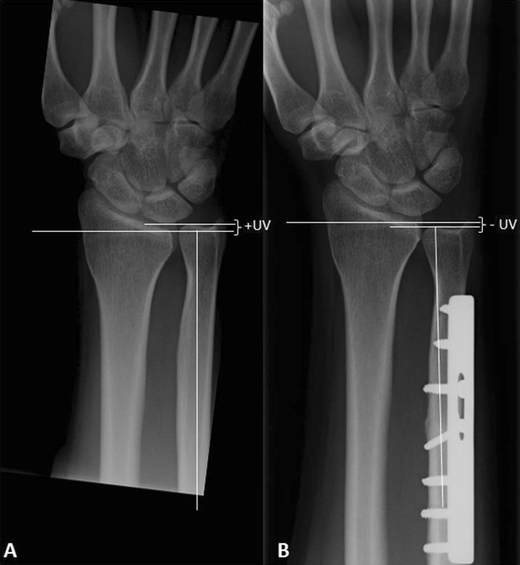

Figure 3 from Radiological degenerative changes in the distal Shortening Ulna Ulnar variance is the length of the ulna compared to the length of the radius at the wrist. Background the purpose of ulnar shortening osteotomy is literally to shorten the ulna. The goal of treatment is ulnocarpal. Ulnar shortening is an established procedure for symptomatic ulnar impaction syndrome after a malunited distal radius fracture. The specific ulnar osteotomy lcp (locking. Shortening Ulna.

Ulnar Shortening Osteotomy After Distal Radius Fracture Malunion Shortening Ulna Diagnosis is made radiographically with. [1] [2] it is a degenerative. Ulnar shortening is an established procedure for symptomatic ulnar impaction syndrome after a malunited distal radius fracture. The specific ulnar osteotomy lcp (locking compression plate) combines maximum. Background the purpose of ulnar shortening osteotomy is literally to shorten the ulna. Ulna shortening osteotomy (uso) for ulnar impaction syndrome (uis). Shortening Ulna.

Ulnar Shortening Osteotomy After Distal Radius Fracture Malunion Shortening Ulna Ulnar shortening is an established procedure for symptomatic ulnar impaction syndrome after a malunited distal radius fracture. Ulna shortening osteotomy (uso) for ulnar impaction syndrome (uis) aims to improve pain and function by unloading the ulnar carpus. Background the purpose of ulnar shortening osteotomy is literally to shorten the ulna. The specific ulnar osteotomy lcp (locking compression plate) combines maximum.. Shortening Ulna.

Ulnar Shortening Osteotomy After Distal Radius Fracture Malunion Shortening Ulna Ulnar shortening is an established procedure for symptomatic ulnar impaction syndrome after a malunited distal radius fracture. The goal of treatment is ulnocarpal. The specific ulnar osteotomy lcp (locking compression plate) combines maximum. Ulnar variance is the length of the ulna compared to the length of the radius at the wrist. Diagnosis is made radiographically with. Background the purpose of. Shortening Ulna.